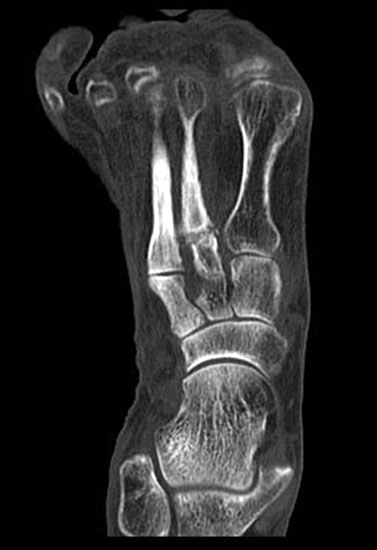

Ein Röntgenbild der Ferse seitlich ist zum Ausschluss knöcherner Pathologien hilfreich.

Im Fall von konservativ vorbehandelten Pseudarthrosen sollte diese nach der Stoßwellentherapie wie eine frische Fraktur nachbehandelt werden, um die stattfindende Neovaskularisation nicht zu gefährden. Diese Ruhigstellung für mehrere Wochen kann dann unterbleiben, wenn im Falle einer vorausgegangenen Osteosynthese keine radiologische Implantatlockerung vorliegt. Analog zur Frakturbehandlung werden Röntgenkontrollen zur Verlaufsdokumentation durchgeführt. Lässt sich das betroffene Areal mit einer konventionellen Röntgenaufnahme nicht zuverlässig einsehen, kann eine Berteilungen mit CT erfolgen, das in dieser Fragestellung der MRT-Untersuchung überlegen ist.

Stressfrakturen sind entweder bei ein- oder mehrmaligen Überlastungen zu beobachten, als auch ohne adäquates Ereignis. Während sportassoziierte Stressfrakturen häufig bei jüngeren, aktiven Patienten zu finden sind, ereignen sich solche ohne konkreten Auslöser oftmals bei Patienten mit reduzierter Knochendichte. Es empfiehlt sich daher in diesen Fällen eine zusätzliche osteologische Befragung und Diagnostik zum Ausschluss einer Osteoporose.

Der Behandlungsalgorhythmus entspricht der Pseudarthrosenbehandlung. Es sollte beachtet werden: Behandlung im hochenergetischen Bereich (Energieflussdichte 0,35-0,6mJ/mm²) unter Anlegen einer Leitungs-oder Allgemeinanästhesie, einmalige Therapiesitzung mit 2000-3000 Impulsen und exakter Ortung der Stressfraktur.